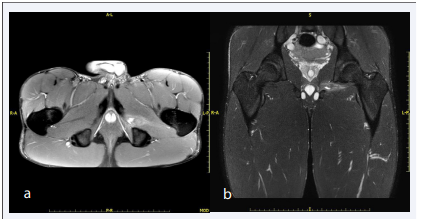

One week after, the patient underwent a second MRI examination which showed, in DWI acquisitions, significantly reduction of the diffusivity narrowing, both in terms of extension and signal, with residual diffusivity reduction only in the most medial portion of the left obturator externus, expression of resolution of the interstitial hemorrhage. There was persistence of edema in the same site, however less extensive than in previous investigation (Figure 2a).

Axial T2 (a) and coronal STIR TSE weighted (b) acquisitions  of the second MRI examination (after seven days) demonstrate the  resolution of the interstitial hemorrhage, with low persistence of  edema, and highlight the appearance of a bursal collection at the  ischiatic insertion of the muscle, with “drop” morphology.

Figure 2: Axial T2 (a) and coronal STIR TSE weighted (b) acquisitions of the second MRI examination (after seven days) demonstrate the resolution of the interstitial hemorrhage, with low persistence of edema, and highlight the appearance of a bursal collection at the ischiatic insertion of the muscle, with “drop” morphology.

Compared to the previous investigation, effusion with a “drop” morphology appeared at ischiatic insertion of the obturator externus. The effusion had a weak hypersignal in SE proton density acquisitions, expression of hemorrhagic component. The effusion had clear margins, well delimited interface towards to the muscle and to the bone, however free of spongious edema.

This last finding might be expression of a bursal collection of the obturator externus (Figure 2b).